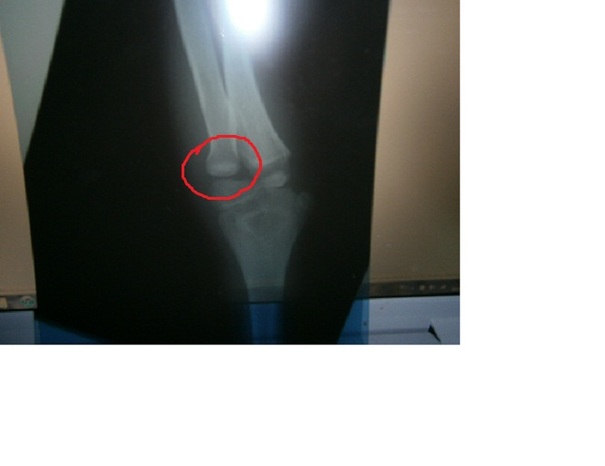

Praticamente circa 8 anni fa sono caduto e mi sono procurato una frattura con lussazione instabile....insomma mi è uscito l'osso; tutti i medici che mi hanno visitato mi hanno detto di non aver mai visto un caso del genere...infatti mi hanno detto che il modo in cui l'osso è uscito era anomalo e che avviene in 1 caso su 1000 (le mie foto sono anche finite su un libro di medicina XD)

Purtroppo ancora oggi l'osso non è rientrato del tutto e non riesco a stender il braccio del tutto (inoltre è un pelo piu piccolo dell'altro).....ma a parte questo ormai non ci faccio piu caso anche perchè non mi da neanche piu problemi...è rimasto solo un "problema" sotto il punto di vista estetico